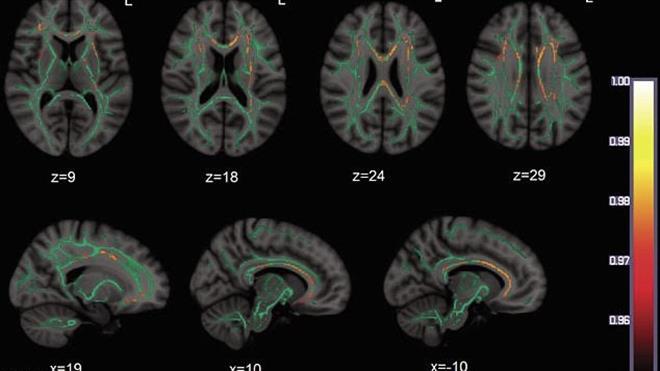

چوار خوێندکاری زانکۆی ڕووتگەرز (Rutgers) ئەنجامی توێژینەوەیەکیان لە کۆنفرانسی دەروونناسی لە بۆستن خستەڕوو، کە دەری دەخات ئەو تەمەنەی مرۆڤ تێیدا فێری زمان دەبێت، بۆ هەتا هەتایە شێوازی پرۆسەکردنی زمان لە مێشکدا دیاری دەکات. ئەم توێژینەوەیە لە ٢٨ی شوباتی ٢٠٢٦ پێشکەشکرا و تیشک دەخاتە سەر لایەنە وردەکانی زمانی ئینگلیزی.

خوێندکارەکان کە لە ژێر سەرپەرشتی پرۆفیسۆر کارین سترۆمسوۆڵ کاریان کردووە، بۆیان دەرکەوتووە کە تەنانەت ئەو کەسانەی لە تەمەنی گەورەیدا بە تەواوی فێری زمانەکە بوون، هێشتا جیاوازییەکی کەمیان هەیە لەگەڵ ئەو کەسانەی لە منداڵییەوە فێری بوون. بۆ نموونە، شێوازی تێگەیشتن لە جێناوەکان و وەڵامدانەوەی پرسیارە ئاڵۆزەکان لە کەسێکەوە بۆ کەسێکی تر دەگۆڕێت بەپێی تەمەنی یەکەم بەرکەوتنی لەگەڵ زمانەکە.

بەشێکی تری توێژینەوەکە باس لە "پڕۆسۆدی" یان ئاوازی قسەکردن دەکات؛ دەرکەوتووە کە ئەو نیشانە دەنگییانەی مرۆڤ بەکاریان دەهێنێت بۆ دیاریکردنی سەرەتا و کۆتایی ڕستەکان، بە توندی بەستراوەتەوە بەو تەمەنەی کە تێیدا فێری زمانەکە بووە. ئەمەش دەری دەخات کە مێشک لە تەمەنی منداڵیدا وەک ئیسفەنج وایە و شێوازی دەنگەکان بە قووڵی تێیدا نەخش دەبن.

ئەم دۆزینەوانە گرنگییەکی زۆریان هەیە بۆ تێگەیشتن لە چۆنیەتی فێرکردنی زمانی دووەم و هەروەها تێگەیشتن لە نەرمی و گۆڕانکارییەکانی مێشک لە ماوەی تەمەنی مرۆڤدا. ئەنجامەکان دەڵێن هەرچەندە مرۆڤ دەتوانێت لە هەر تەمەنێکدا فێری زمان بێت، بەڵام ئەو "پەنجەمۆرە" زمانییەی لە منداڵیدا دروست دەبێت، تا کۆتایی تەمەن دەمێنێتەوە.